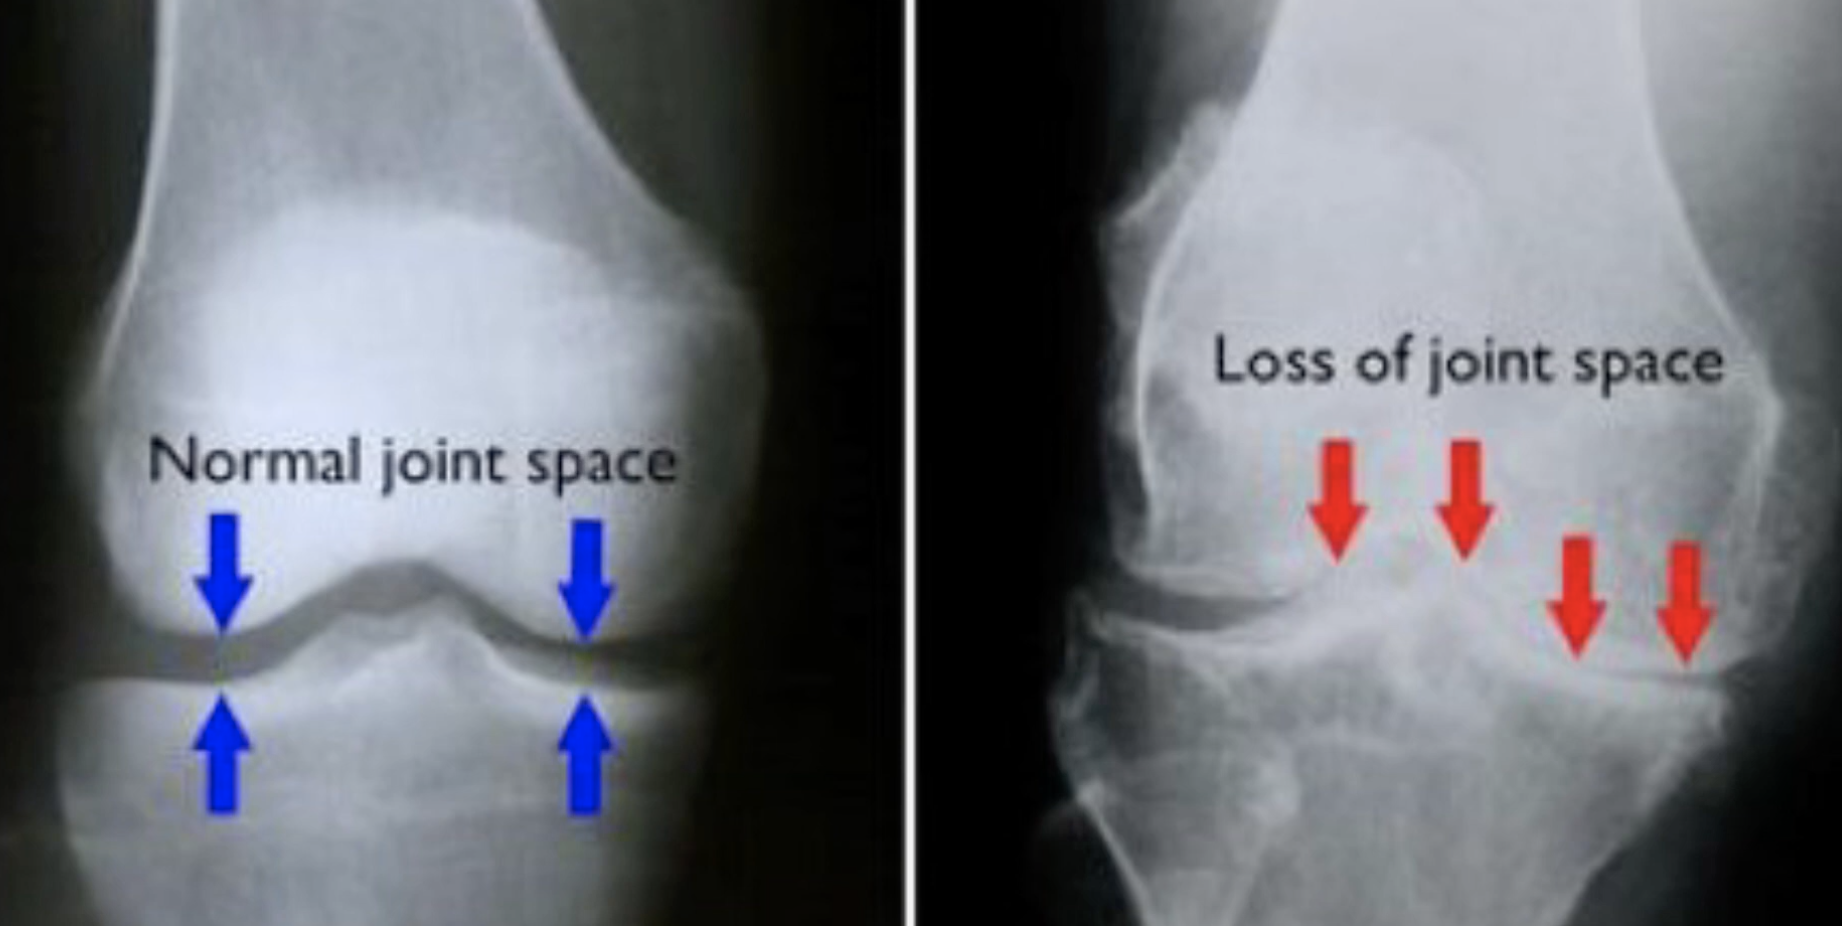

骨刺一般情況不會引起疼痛,大部分情況下,導致長期痛症的原因包括姿勢問題、運動發力錯誤、勞損等,而在關節炎情況比較嚴重時,可能會導致關節面摩擦增多而導致疼痛和活動受限。